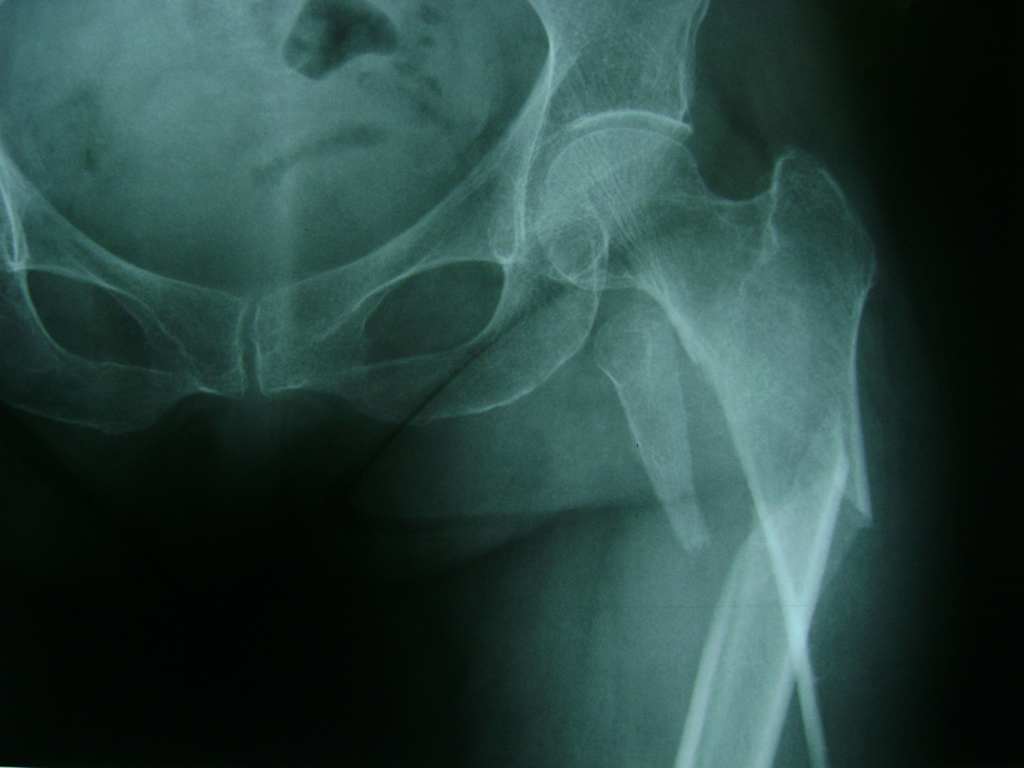

La cirugía de fractura de cadera se realiza para reparar una ruptura en la parte superior del hueso del muslo. Este hueso se denomina fémur.

Es parte de la articulación coxofemoral. Si una fractura de cadera no recibe tratamiento, es posible que deba permanecer en una silla o en la cama.

Esto puede llevar a otros problemas de salud potencialmente mortales, sobre todo si usted es una persona mayor.